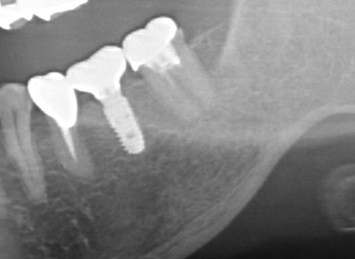

下顎管まで近いケースショートインプラントと垂直GBR(骨造成)で対応した →インプラント埋入

治療前

治療後

施術名 | インプラント埋入垂直GBR(骨造成) |

---|---|

主訴 | 噛めない |

施術の副作用(リスク) | 感染脱落 |

施術の価格 | 1本GBR5万~10万(税抜き)+インプラント埋入補綴まで35万(税抜き) FGG5万 |

コメント | 下顎管まで近いケースショートインプラントと垂直GBR(骨造成)を同時に行いました |